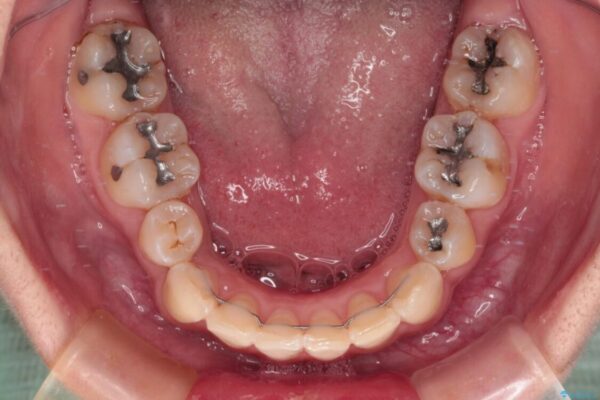

内側に倒れ込んだ歯や下の前歯が隠れてしまうほどの咬み合わせを改善したいとのことで来院された患者様です。

下顎の叢生を解消するために抜歯が必要であり、奥歯の咬み合わせや口元の印象から、上顎も同様に抜歯と判断し、上下左右の第1小臼歯4本抜歯してワイヤー装置にて矯正治療を行うこととしました。

治療前

• デコボコと深い咬み合わせ ワイヤー装置での抜歯矯正 治療前画像